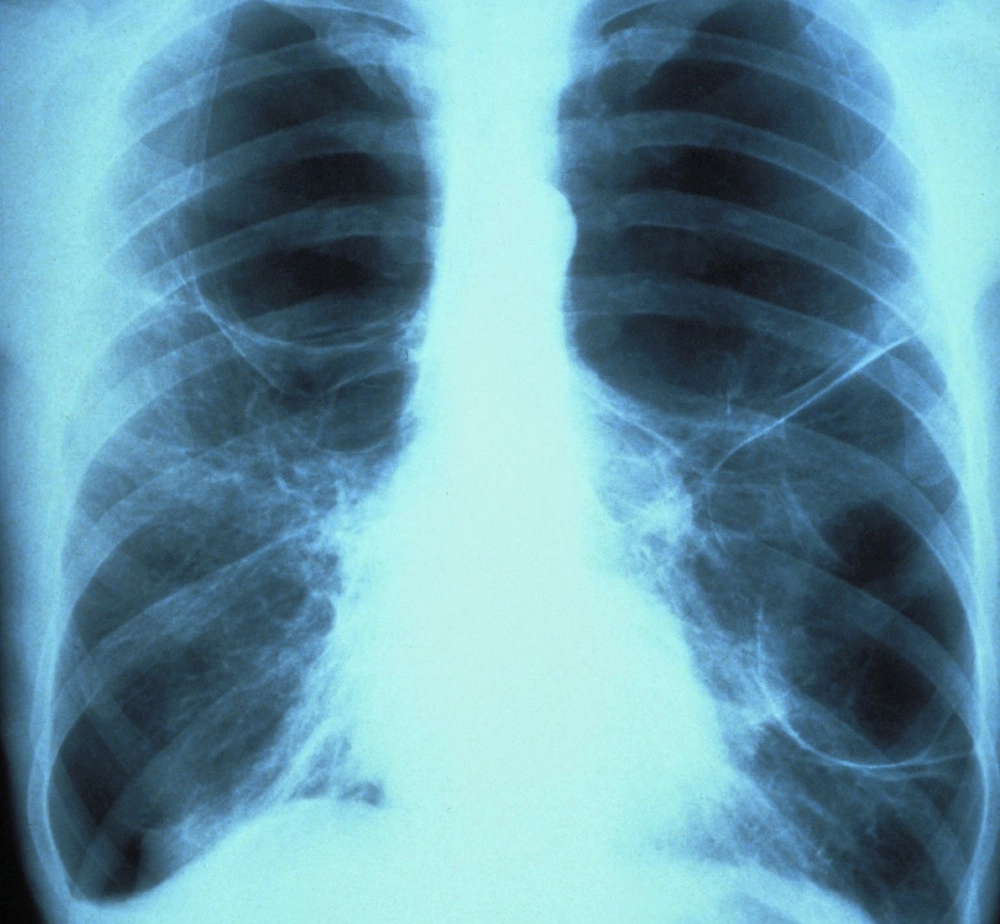

Lung cancer rates are increasing among women and people who have never smoked, a new study finds.

The study found non-smokers made up 11.9 percent of the lung cancer cases, up from 7.9 percent in 2000. And the percentage of female lung cancer patients jumped from 16 percent to 24.4 percent over the decade.

Among women with a history of smoking, lung cancer rates barely changed over those 10 years, hovering around 65 percent. Meanwhile, this figure decreased in men, while the rate of male lung cancer patients who had never smoked increased, the researchers said.

This change — 58 percent with stage 4 in 2010 compared with 43 percent in 2000 — might reflect new classifications of different stages of the disease, the researchers said. They also found big changes in the type of cancer being diagnosed. The rate of people developing adenocarcinoma, a form of non-small cell lung cancer, jumped from 35.8 percent to 53.5 percent over the decade.